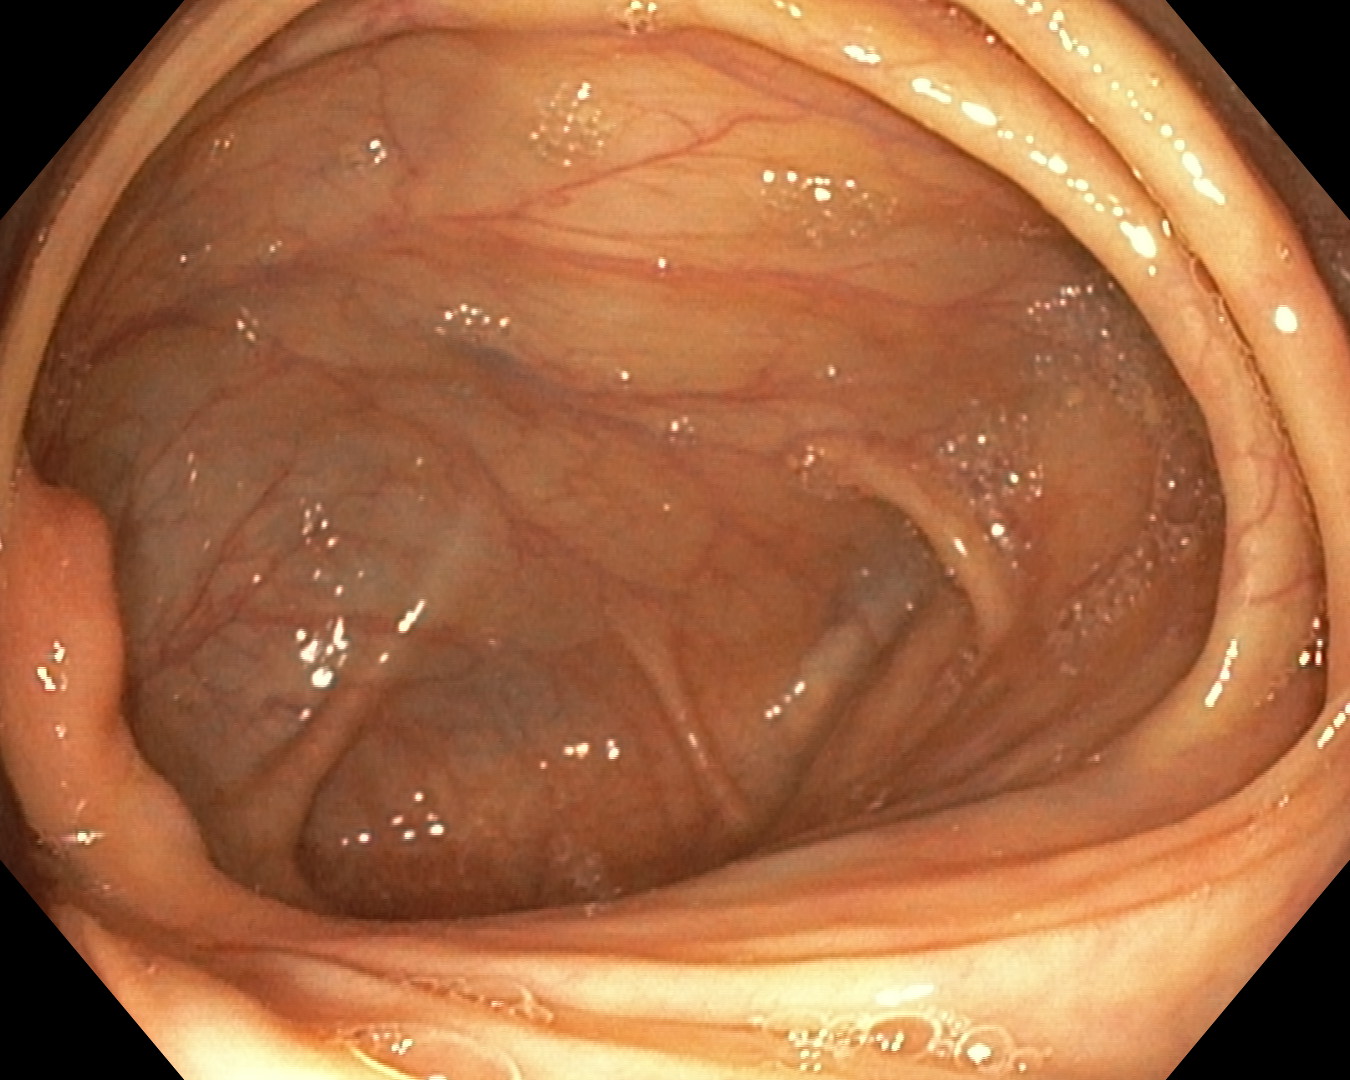

As part of the EndoCV2021 challenge (https://endocv2021.grand-challenge.org/), we were tasked with creating machine learning models that automatically segment polyps [11, 12, 13] in video frames collected from real-world endoscopies. This is a complex task as polyps come in various shapes and sizes, where some (e.g., flat lesions) are barely detectable by even the most experienced endoscopists. Figure 1 shows some of the more difficult examples taken from EndoCV’s development dataset [10] provided by the challenge organizers. The challenge presented two separate tasks, the detection generalization challenge and the segmentation generalization challenge. We participated in the segmentation generalization challenge, where we achieved the best results among 13 other competitors in both rounds. The code for the experiments presented in this paper is available on GitHub111https://github.com/vlbthambawita/divergent-nets.